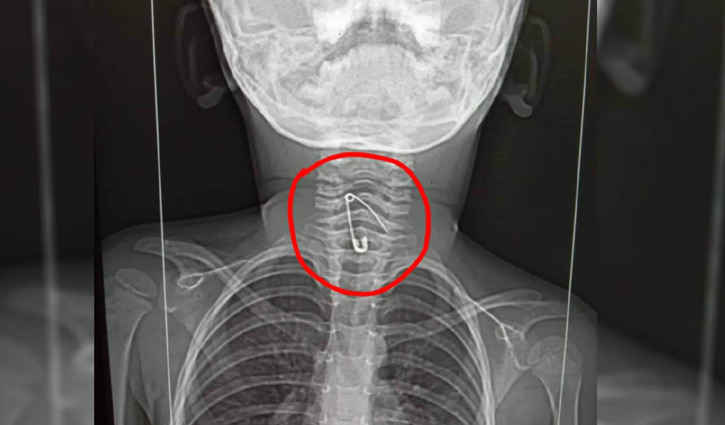

গলায় সেফটিপিন নিয়ে হাসপাতালে শিশু

নাটোরের লালপুরে মায়ের হাতে নুডুলস খাওয়ার সময় জিদনী (৩) নামের এক শিশুর গলায় সেফটিপিন আটকে গেছে। এক্স-রে করার পর বিষয়টি নিশ্চিত করেছেন শিশুটির চাচাত ভাই হাসান আলী।

শুক্রবার (২৬আগস্ট) শিশুটির গলা এক্স-রে করা হয়।

রাজশাহীর ইসলামী ব্যাংক হাসপাতালের মেডিক্যাল টেকনোলজিস্ট শফিকুল ইসলাম বলেন, এক্স-রে রিপোর্টে শিশুটির গলায় সেফটিপিন দেখা গেছে। ভুক্তভোগীর স্বজনদের সঙ্গে কথা বলে জানতে সেপটিপিনটি নুডলসের মধ্যেই নাকি ছিল। নুডলস খাওয়ানোর সময় ভুলবশত সেফটিপিন চলে যায়।

জানা গেছে, বৃহস্পতিবার সন্ধ্যায় মা জুলেখা বেগম নুডুলস খাওয়ানোর সময় অসাবধানতাবশত শিশুটির গলায় সেফটিপিন আটকে যায়। এসময় শিশুটি অসুস্থ হয়ে পড়লে তাকে পার্শ্ববর্তী বাঘা উপজেলা স্বাস্থ্য কমপ্লেক্স নেওয়া হয়। অবস্থার অবনতি হলে সেখান থেকে রাতেই রাজশাহী মেডিক্যাল কলেজ হাসপাতালে ভর্তি করানো হয়। সেফটিপিনটি বের করা না গেলেও শিশুটি বর্তমানে কিছুটা সুস্থ রয়েছে।

শিশু জিদনীর চাচাতো ভাই হাসান আলী জানান, নুডুলস খাওয়ানোর পরপরেই বমি করতে শুরু করে জিদানী। পরে তাকে হাসপাতালে ভর্তি করানো হয়। রাজশাহী মেডিক্যাল কলেজ হাসপাতালে ভর্তি করলে এখানকার চিকিৎসকরা সেফটিপিন বের করার মেশিন না থাকায় ঢাকায় নেওয়ার পরামর্শ দেন। শুক্রবার জিদনীর গলার এক্স-রে করানো হয়েছে।